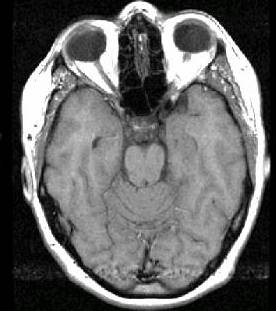

| Substance |

T1 weighted |

| Water/Vitreous/CSF |

black |

| Fat |

White |

| Muscle |

Grey |

| Air |

| Fatty bone marrow |

| Brain: White matter |

Light Grey |

| Brain: Grey matter |